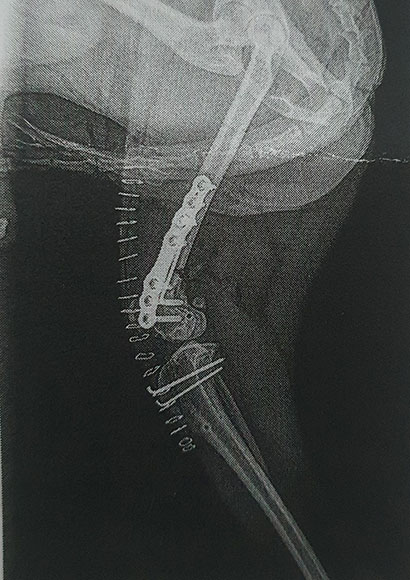

Mittlerweile konnte nun auch schon die erste Röntgenkontrolle stattfinden, mit der der Tierarzt sehr zufrieden war- der Operation des zweiten Beines steht erfreulicherweise also nichts im Wege.

Röntgen

Nach eingehenden Untersuchungen steht es nun leider fest,

Yuki muss unters Messer und das gleich zweimal.

Er hat in beiden Hinterläufen eine massive Fehlstellung der Beinachse, die zusätzlich zu einer Patellaluxation Grad IV führte.

Diese Fehlstellung muss jetzt schnellstens behoben werden, denn wenn er nicht operiert wird, wird er in 2-3 Jahren keinen Schritt mehr schmerzfrei gehen können.